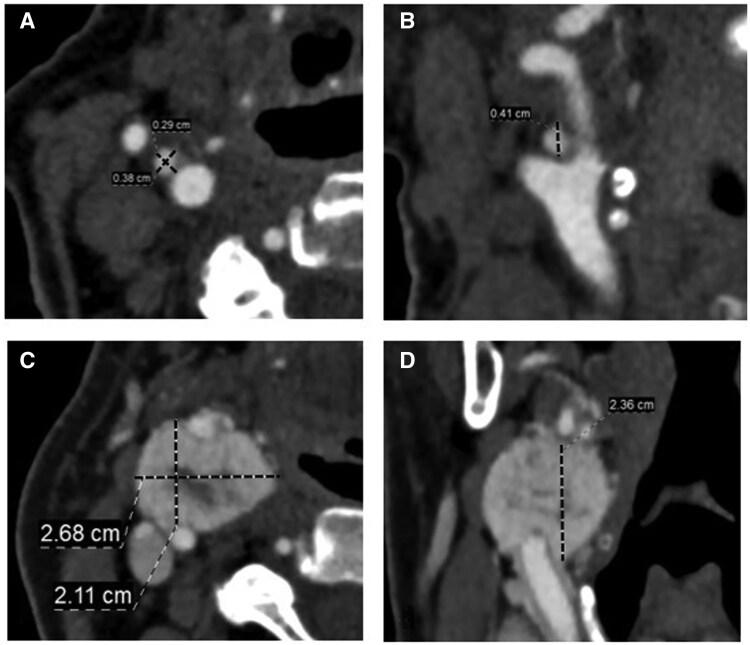

Sympathetic nervous system hyperactivation in chronic conditions, such as hypertension and metabolic syndrome, can lead to carotid body (CB) hyperplasia, potentially mimicking small carotid body tumours (CBTs) in radiological evaluations. This study aimed to investigate CT angiography (CTA) findings to differentiate CBTs from non-neoplastic CBs.

Significant differences between the CB and CBT groups were found in gender, smoking status, and shape (P < .01), while age, location, hypertension, and diabetes mellitus showed no association (P > .05). The CBT group had significantly higher density, standard deviation, and density ratios (P < .001). Multivariate analysis, adjusted for age, gender, and smoking, showed that saddle shape, standard deviation ≥21.5, and density ratio ≥0.5603 predicted CBT diagnosis with 92.6% sensitivity and 99.3% specificity.

CONCLUSIONS

Specific CTA findings, including saddle shape, increased density, and standard deviation, can effectively differentiate small CBTs from non-neoplastic CBs, offering a novel approach to improving radiological diagnostics in cases with CB hyperplasia.

在高血压和代谢综合征等慢性疾病中,交感神经系统的过度激活可导致颈动脉体(CB)增生,在影像学评估中可能会被误诊为小的颈动脉体瘤(CBT)。本研究旨在探讨CT血管造影(CTA)表现,以区分CBT与非肿瘤性CB。

CB组和CBT组在性别、吸烟状况和形状方面存在显著差异(P < 0.01),而年龄、位置、高血压和糖尿病无相关性(P > 0.05)。CBT组的密度、标准差和密度比显著更高(P < 0.001)。在对年龄、性别和吸烟进行校正的多变量分析中,鞍形、标准差≥21.5和密度比≥0.5603预测CBT诊断的敏感性为92.6%,特异性为99.3%。

鞍形以及密度和标准差增加是提示CBT诊断的表现。所提出的影像学特征可能有助于提高小CBT与非肿瘤性CB的鉴别诊断,特别是在CB增大但缺乏典型肿瘤特征的病例中。

特定的CTA表现,包括鞍形、密度增加和标准差增加,可有效区分小CBT与非肿瘤性CB,为改善CB增生病例的放射学诊断提供了一种新方法。